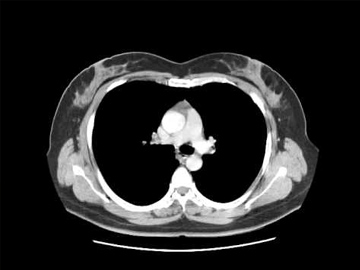

TAC de tórax